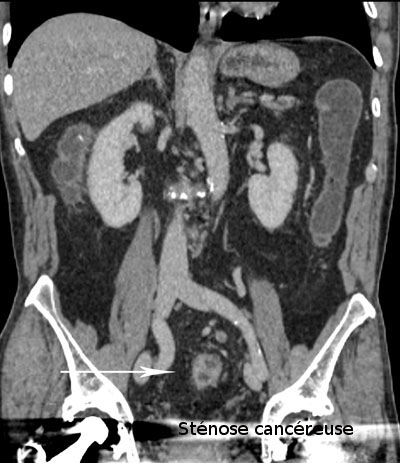

Son indication est essentiellement le diagnostic d'un cancer colorectal et de polypes, il est proposé en alternative à la coloscopie devant des symptômes évoquant un cancer colique, en particulier chez les sujets âgés ou fragiles pour lesquels il est préférable de se dispenser d'une anesthésie générale en première intention. Cette technique permet de faire le diagnostic du cancer et le bilan complet de recherche d'une métastase, en particulier hépatique ou pulmonaire.

Lésion villeuse du segment distal du sigmoïde (images 1, 2 et 3)